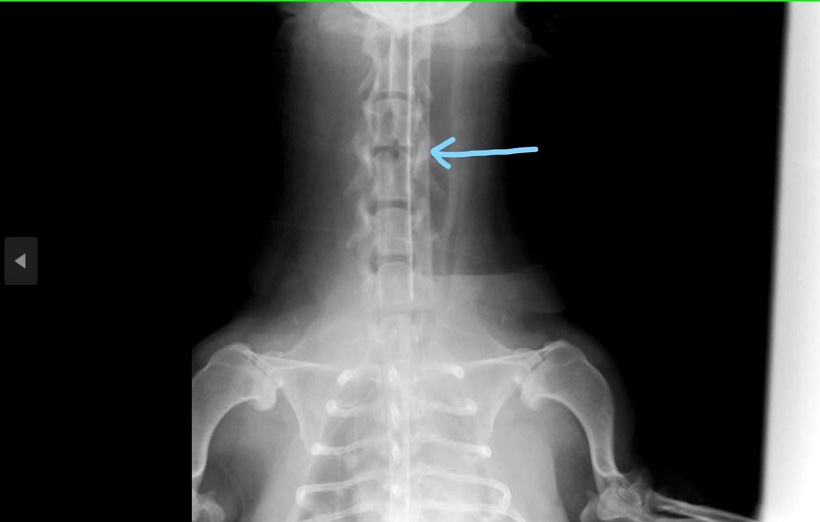

当院にはMRIがないため、脊髄造影X線検査での検査になります。

脊髄はX線では通常写りませんが、造影剤を入れることで浮かび上がらせることができます。

写真で首の骨の中に二重の線が見えるかと思います。

この部分が脊髄です。

そして、一部山なりに凹んでいる部分が、椎間板ヘルニアを起こして首の下の方から脊髄が押されている部分です。

写真の矢印の部分が、骨を削って穴をあけた部分です。